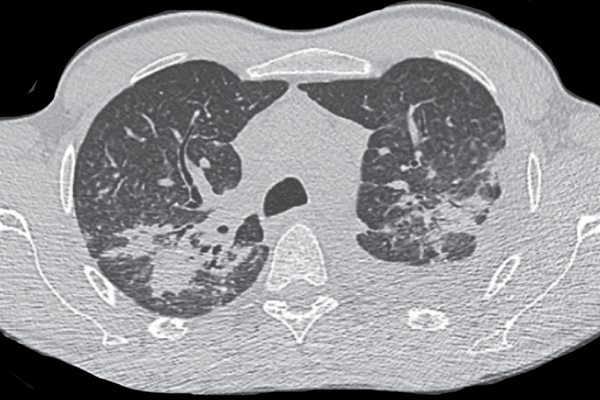

O género Pandoraea é constituído por bacilos Gram-negativo não fermentadores multirresistentes, maioritariamente isolados em amost...